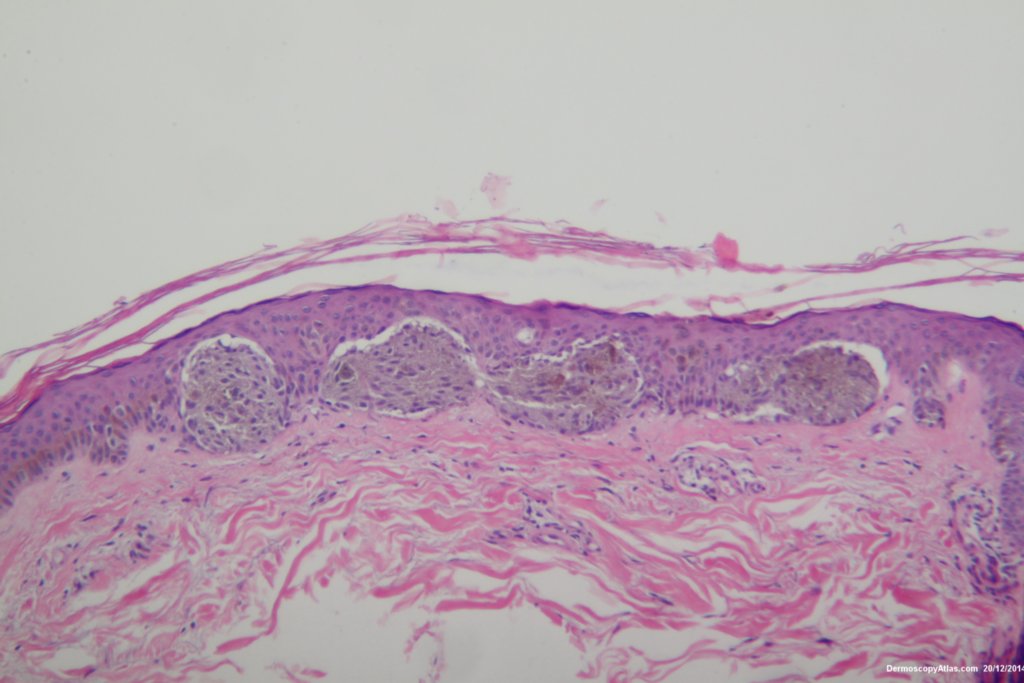

The dermatoscopy shows dark clods of varying sizes both peripheral and central. These represent nests of rapidly growing melanocytes. The lesion is dark because the nests press high into the epidermis giving a black colour. Sometimes cells are extruded into the stratum corneum exagerating the dark colour.

The histopathology shows nests of epitheliod and spindled cells with lots of melanin in them. There are a few melanophages in the dermis. There is no inflammatory reaction beneath this lesion. There were no mitoses. This is just a junctional lesion ie no nests of cells in the dermis.